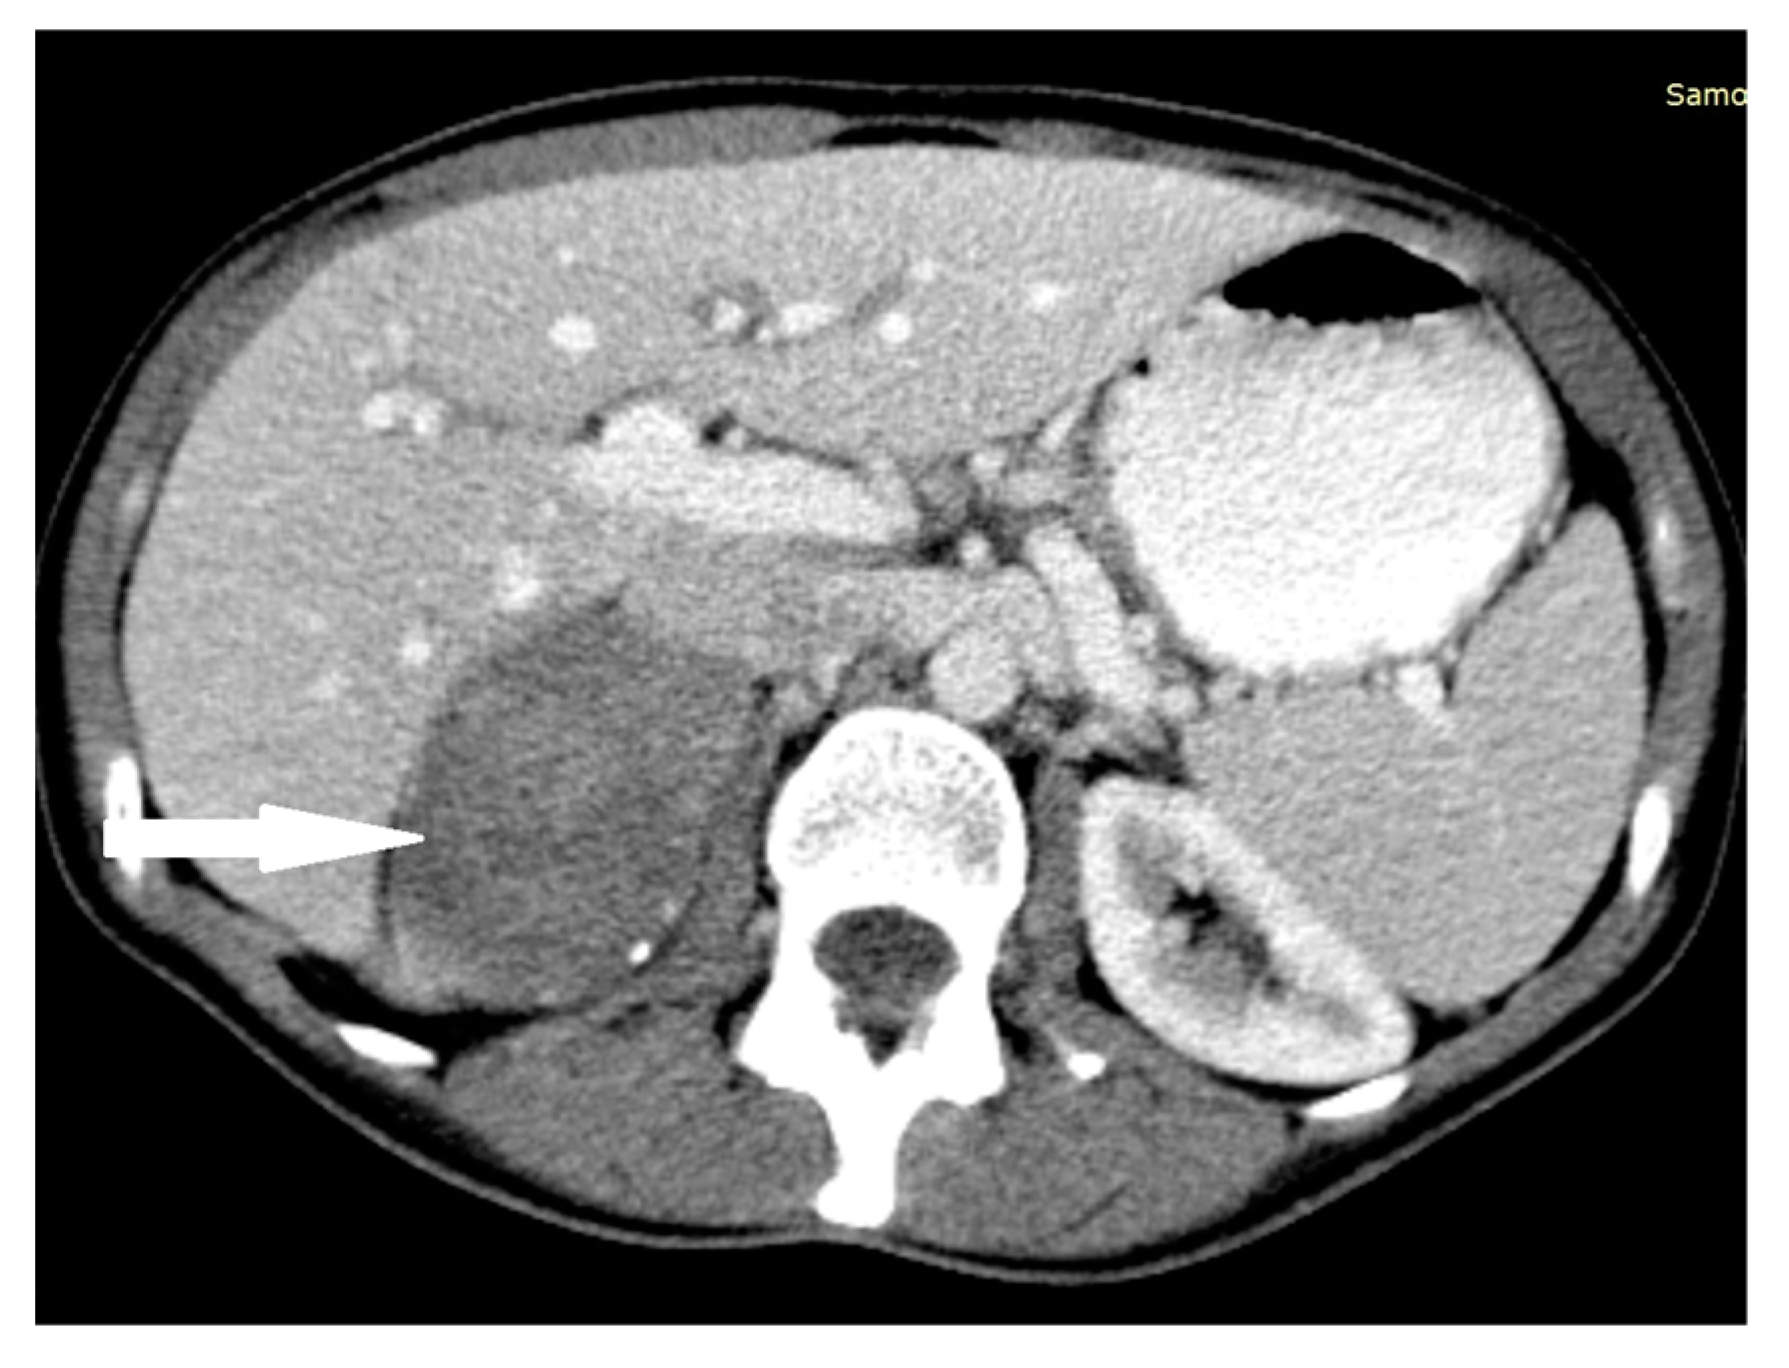

2.1. Case 1